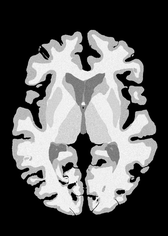

4.2 Registration to a 100 micron ex-vivo brain MRI volume

To showcase the efficacy of our method on real large scale images, we register a 250 in-vivo MRI image (Lüsebrink et al., 2017) to a 100 ex-vivo FLASH human brain volume (Edlow et al., 2019). This represents an inverse problem with more than 11.2B optimizable parameters (compared to 20M for clinical datasets), or 44.8GB of GPU memory. The entire problem does not fit on most GPUs, necessitating distributed multimodal registration. We optimize a composite transform - affine followed by a diffeomorphic mapping; details can be found in Section E.1. Multimodal deformable registration took 58 seconds on 8 NVIDIA A6000 GPUs, which is unprecedented at this resolution. Fig. 6 shows qualitative results, highlighting the ability to register highly detailed structures such as cerebellar white matter; these structures are not visible at macroscopic scales. The resultant advantages of performing registration at this scale can allow researchers to characterize the neuroanatomy at microscopic resolutions and allow morphometric analysis of cortical layers and subcortical nuclei among other structures.